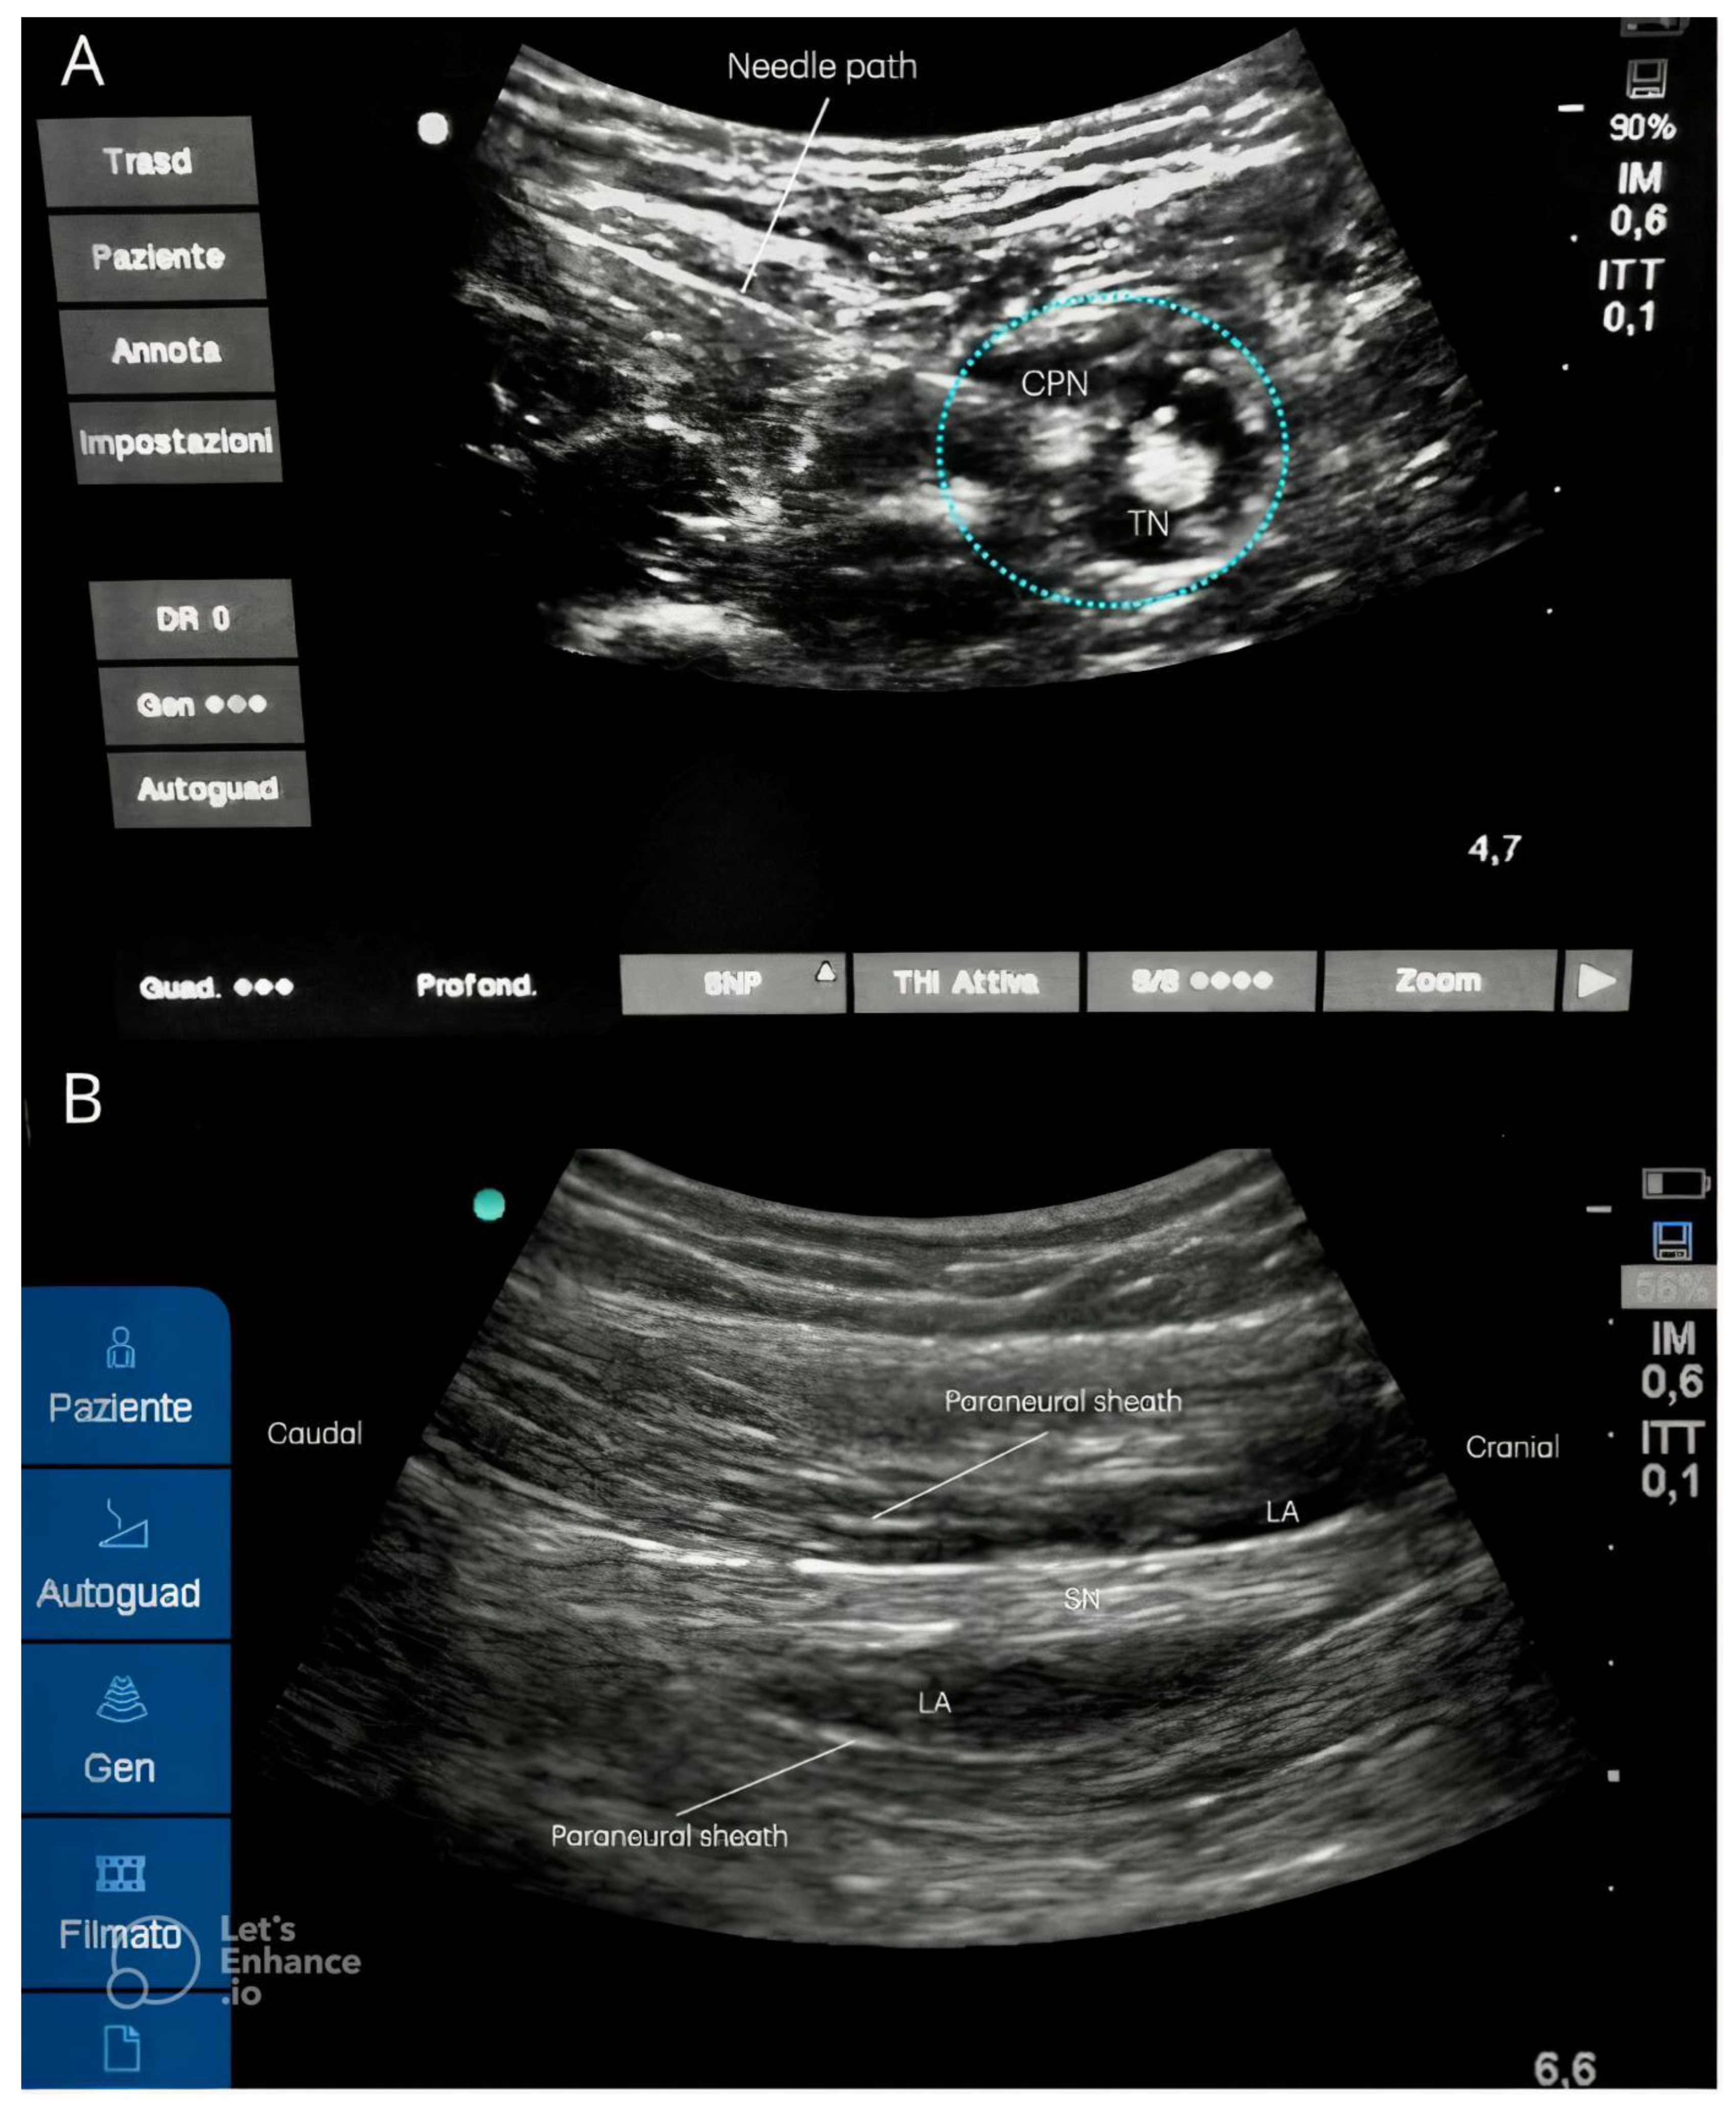

- The popliteal approach is limited by significant anatomical variability; in fact, in 53.33% of cases, the SN divides near the upper angle of the popliteal fossa; in 26.66% of cases, the division occurs in the middle of the posterior thigh, while 13.33% of cases show the division at the upper one-third of the posterior thigh; only in 6.66% of cases does the CPN pass through the piriformis muscle, with the TN situated below the piriformis muscle [15]. Moreover, the popliteal approach requires the patient to be in prone position, rendering the procedure uncomfortable for those patients affected by lower limb fractures (Figure 4A) [2].

- The original lateral approach requires the patient to adopt a supine position with the leg bent, a lateral to medial needle direction, and the probe placed below the thigh with a posterior to anterior ultrasound beam used, similar to the popliteal approach performed with the patient in a supine position. The challenges consist of the uncomfortable position adopted by both the patient, unable to flex their leg, and the anesthetist (Figure 4B) [7,9,11].